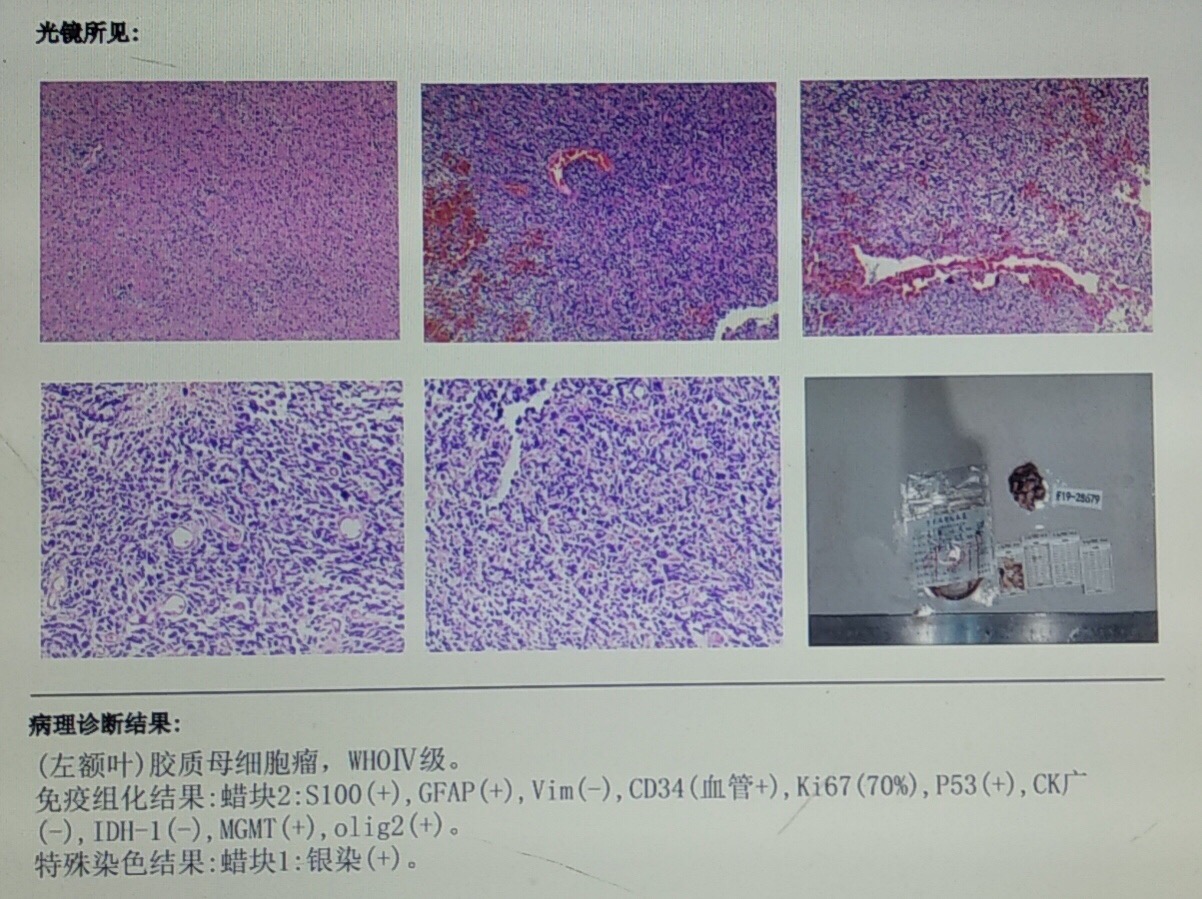

男性患者,53岁,主诉:反复头痛伴恶心一周,突发意识丧失一次。入院查体:神经体统无阳性体征。入院头颅MRI:左额叶胼胝体区囊实性占位,不均匀强化,考虑高级别胶质瘤;长程视频脑电监测提示左侧中央区、顶区、后颞区见中等量低-中-高波幅痫样放电。术前诊断:1.左额叶胼胝体区占位病变;2.继发性癫痫,入院给予降颅压及抗癫痫处理,积极完善术前准备后于2019年12月3日全麻下完成手术,术中行B超引导下切除肿瘤。术后患者无肢体功能及语言功能障碍,复查头颅核磁肿瘤全切,一周后出院开始放化疗治疗。

总结:肉眼下胶质瘤与周围正常脑组织很难找到明显边界,术中超声能实时明确肿瘤范围、肿瘤切除程度及肿瘤与脑组织边界,手术过程中对于正常脑组织起到很大保护作用,特别是对于功能区的胶质瘤切除,周围脑组织的保护显得尤为重要,借助于术中超声,既能保护正常脑组织,又能最大程度切除肿瘤,结合术后放化疗治疗,延长肿瘤复发时间。